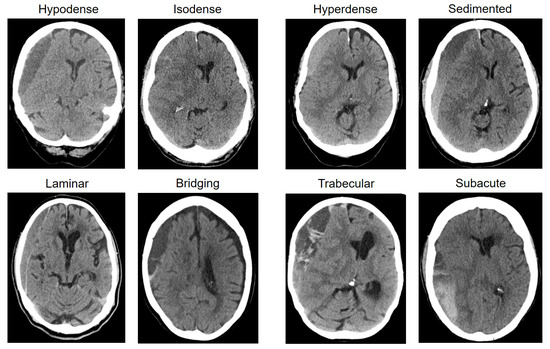

| Internal architecture—no. (%) | 0.730 | |||

| Homogenous hypodense | 81 (20.4) | 51 (19.9) | 30 (21.1) | |

| Homogenous isodense | 86 (21.6) | 62 (24.2) | 24 (16.9) | |

| Homogenous hyperdense | 22 (5.5) | 16 (6.3) | 6 (4.2) | |

| Sedimented | 27 (6.8) | 16 (6.3) | 11 (7.7) | |

| Laminar | 51 (12.8) | 32 (12.5) | 19 (13.4) | |

| Bridging | 38 (9.5) | 22 (8.6) | 16 (11.3) | |

| Trabecular | 67 (16.8) | 41 (16.0) | 26 (18.3) | |

| Subacute | 26 (6.5) | 16 (6.3) | 10 (7.0) | |